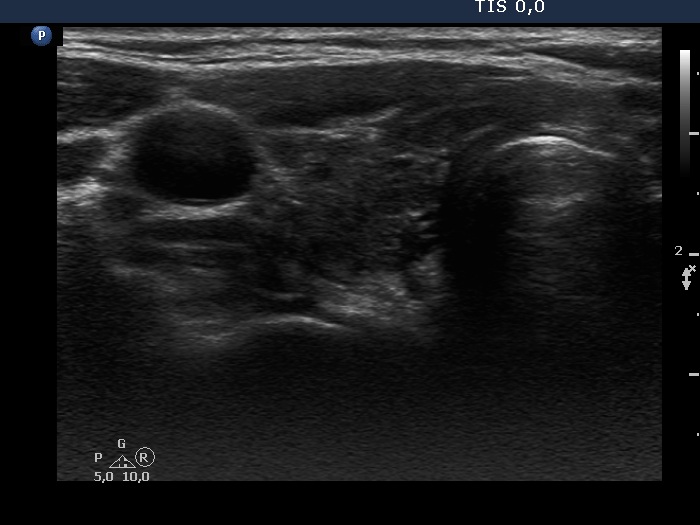

Intact right lobe without any pathological finding and benign hyperplastic nodules in the left lobe (histological diagnosis) - case 803

Left lobe

Both the pseudonodule in the right lobe (upper images) and the benign nodule in the left lobe (lower images) have numerous pale granules and lines which correspond to the normal architecture of the thyroid and correspond to a connective tissue. The finding of a few more bright granules and lines are the ultrasound presentation of a thickened connective tissue.